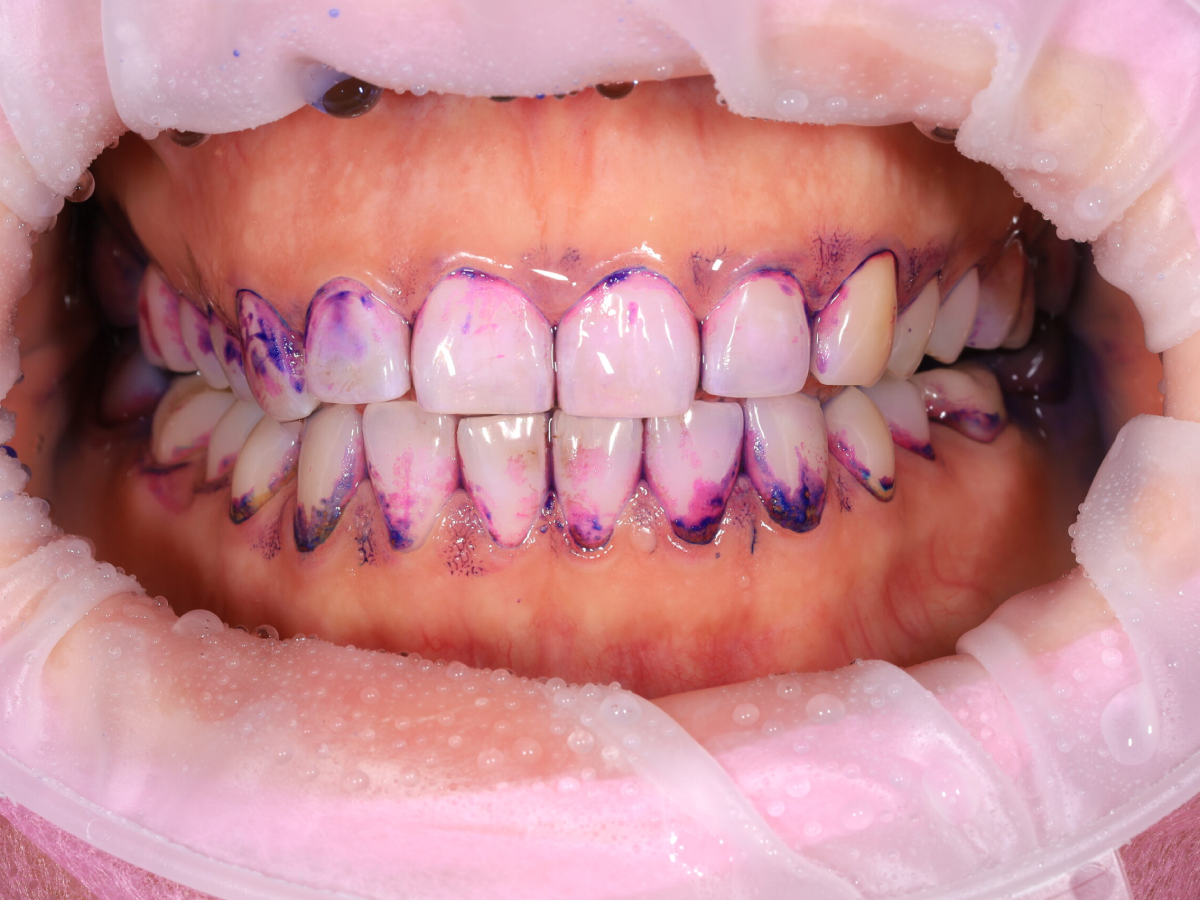

Pełna higienizacja: usunięcie kamienia i osadu (scaling, piaskowanie).

Profesjonalne czyszczenie zębów: scaling, polerowanie i fluoryzacja.

Metamorfoza uśmiechu: usunięcie przebarwień i kamienia nazębnego.